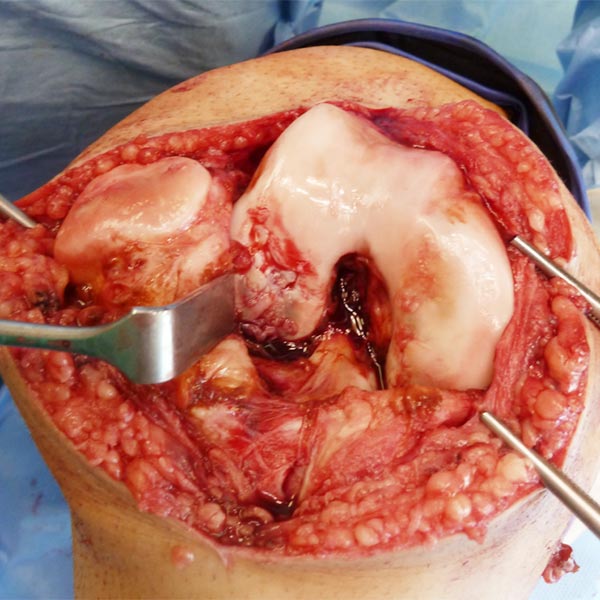

Intraoperative image after removal of the synovium and the intra-articular venous malformation. Remnants of the venous malformation are still present above the anterior cruciate ligament. Extensive cartilage damage at the lateral femoral condyle.

The venous malformation was then completely removed, and the anterior cruciate ligament is now fully visible and exposed. The cartilage damage was covered and treated by a so-called extracellular matrix.